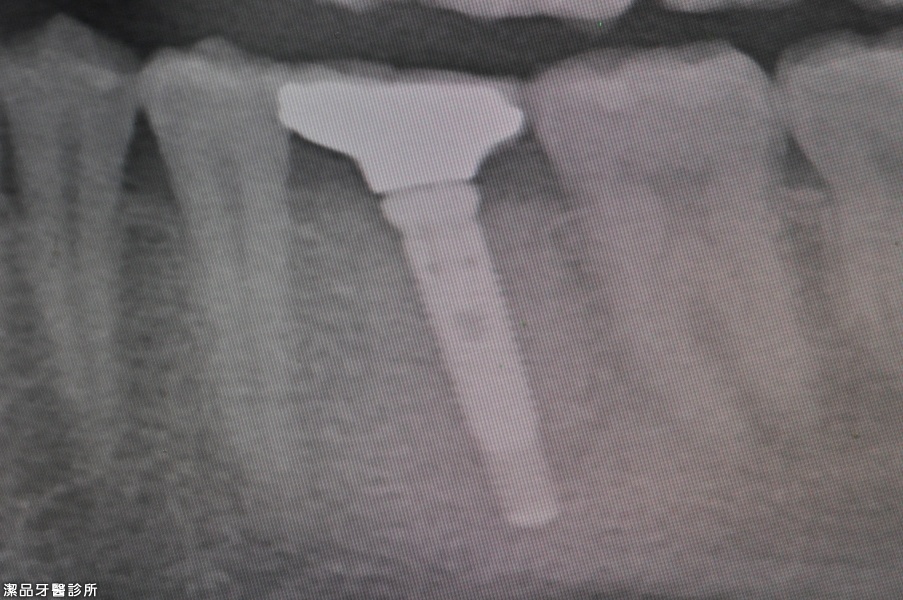

植牙後3個月完成治療

植牙周圍都是健康的骨頭